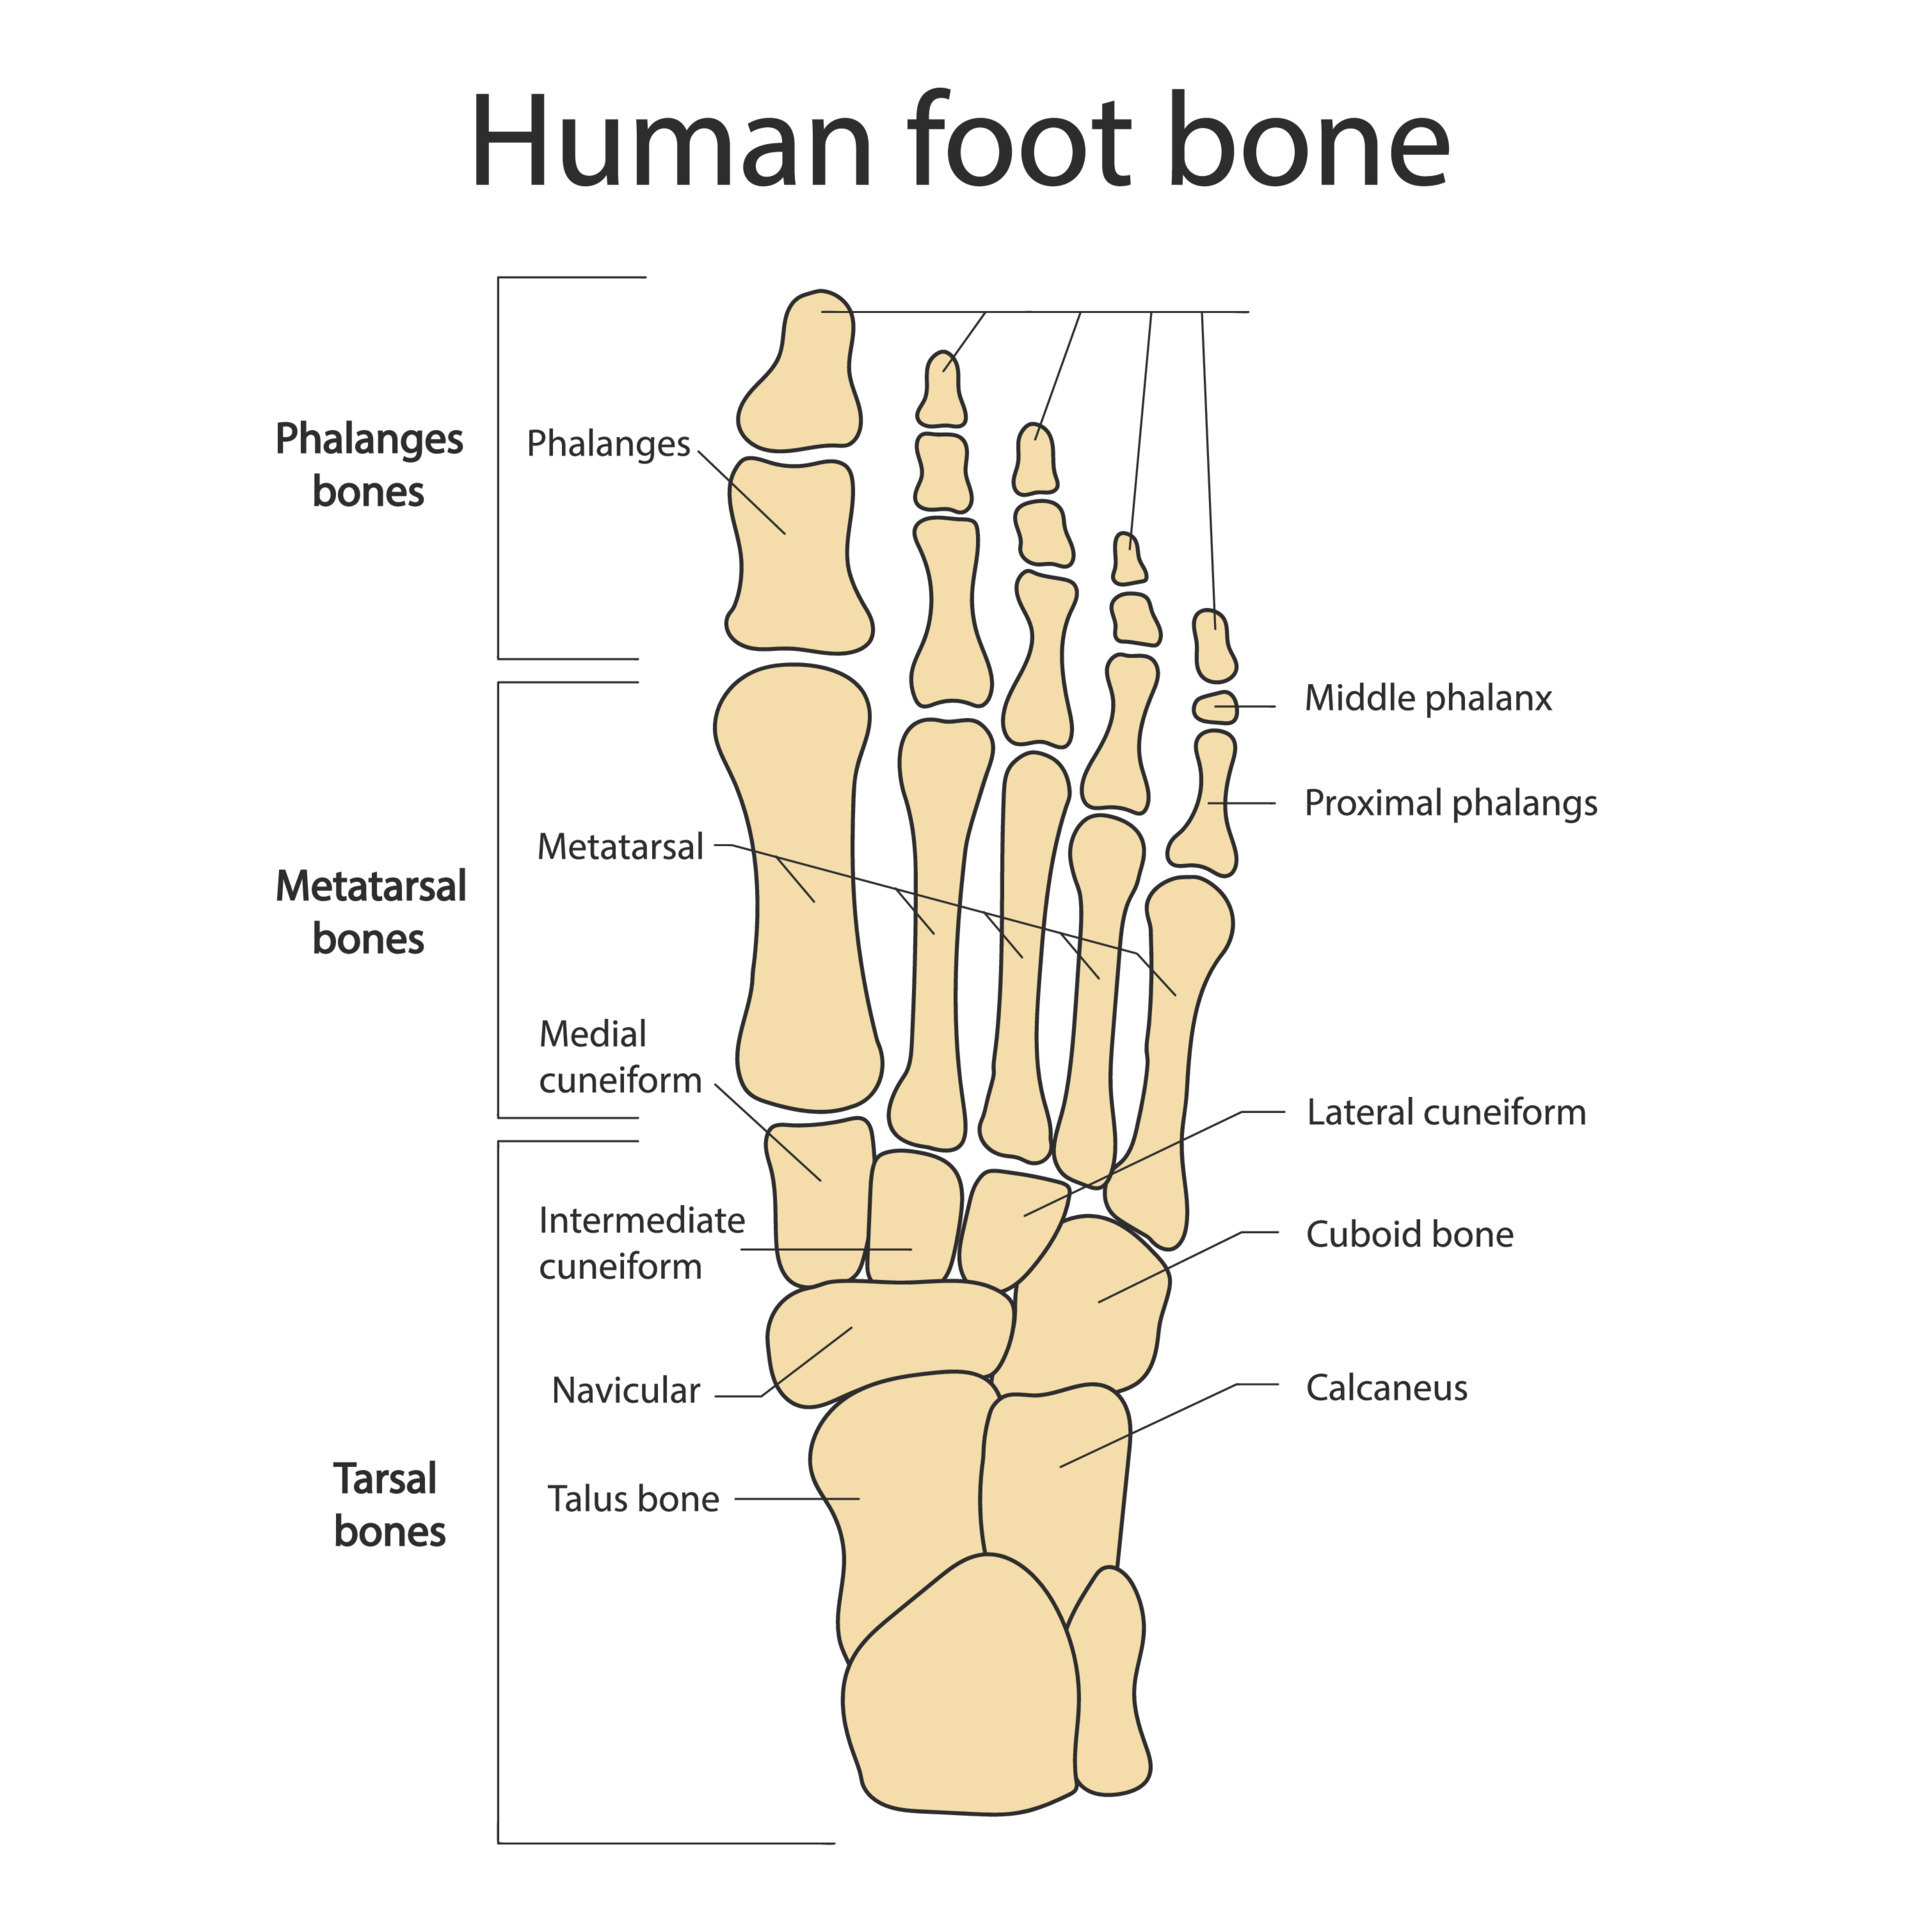

anatomia piede Bones of the human foot with the name and description of all sites

www.alamy.itBones Of The Human Foot With The Name And Description Of All Sites

www.alamy.itBones Of The Human Foot With The Name And Description Of All Sites

focusedcollection.comBones Of The Human Foot With The Name And Description Of All Sites

focusedcollection.comBones Of The Human Foot With The Name And Description Of All Sites